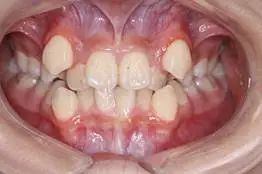

3、牙齒前突:當(dāng)前牙的傾斜度不良,無(wú)論是外突,還是向內(nèi)傾斜,都會(huì)影響到牙齒和面部的美觀。如圖3所示的上牙前突,上下前牙之間咬合距離大,專業(yè)術(shù)語(yǔ)就是深覆蓋。如圖3所示.

3,上前牙外突,唇向傾斜,上下牙之間咬合距離大